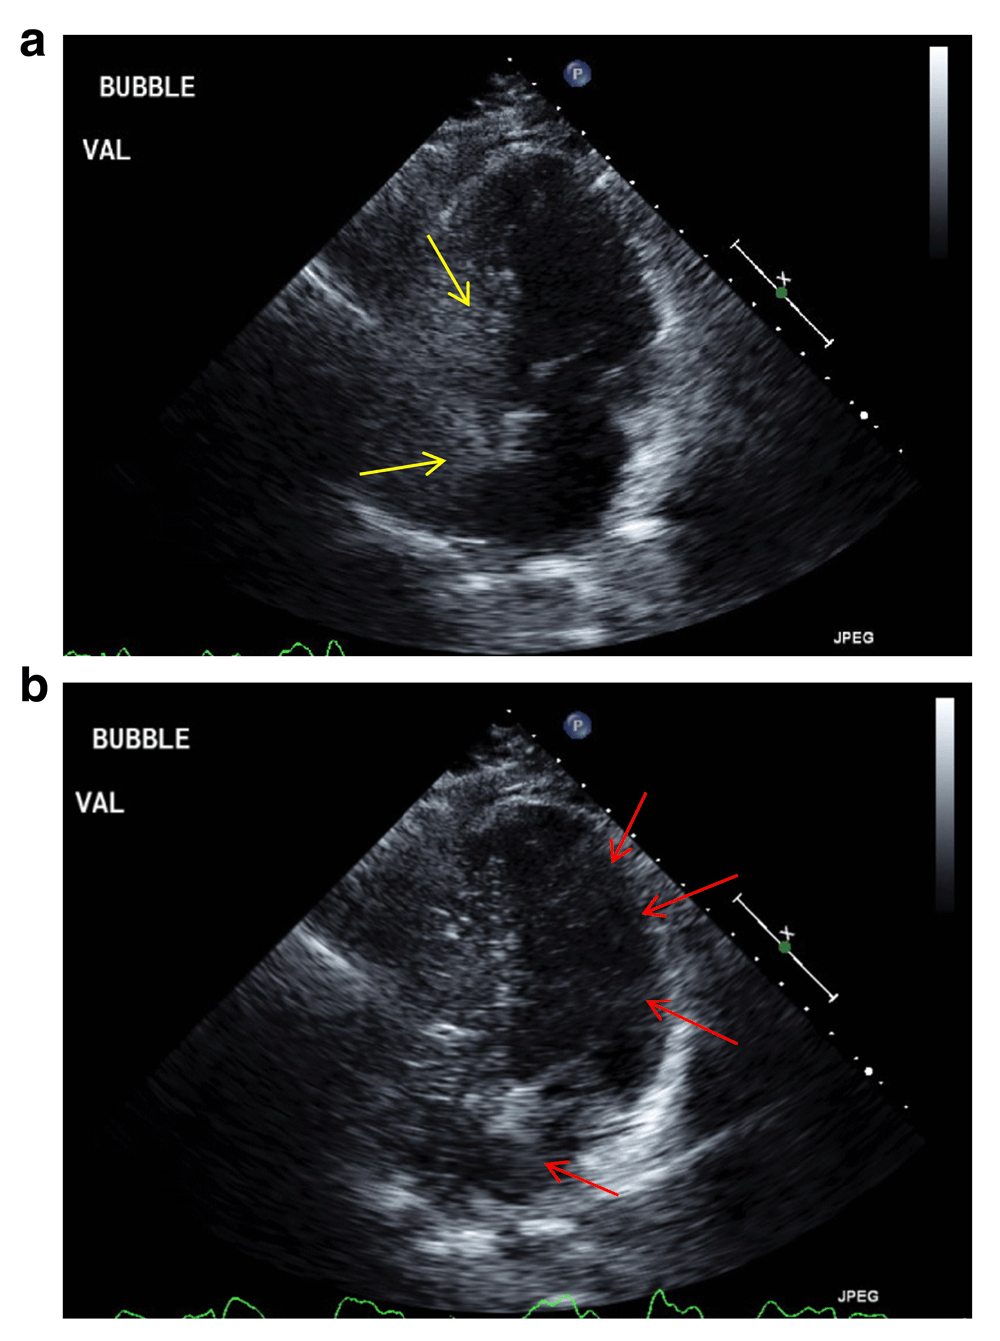

An 86 year old retired latina woman with a past medical history of COPD, bronchiectasis, MAI infection (not previously treated), diabetes mellitus, hyperlipidemia, and hypertension presented with two weeks of worsened dyspnea and non-productive cough. She reported a baseline of daily shortness of breath with an exercise tolerance of 3 blocks, but over the two weeks prior to her presentation it decreased to the point where she would feel dyspneic when walking around her apartment. Interestingly she stated that she also generally felt more short of breath while seated than when lying down, and also cited a worsening cough over this time course productive of green sputum. Her exam on presentation was significant for an oral temperature of 101.4 degrees Fahrenheit, oxygen saturation of 84% on room air, tachypnea and coarse crackles appreciated diffusely on lung examination. Her blood-work was notable for a white blood cell count of 19.8 k/µL, with multiple diffuse small nodular opacities seen on chest x-ray. She was started on levofloxacin for treatment of a presumed bronchiectasis flare along with oxygen therapy via nasal cannula in addition to other supportive treatments. Although her fever, leukocytosis, and cough improved with antibiotics (further supporting a diagnosis of bronchiectasis flare), her dyspnea and hypoxemia persisted. Consequently, a chest computerized tomography (CT) scan was ordered which showed the same extensive nodularities seen on chest x-ray, but also elucidated a nodular liver consistent with cirrhosis. While her platelet count, transaminases, bilirubin, and prothrombin time were all normal and she had no ascites or other edema on exam, she did however have spider angiomas. Further chart review done at that time revealed that she had known cirrhotic characteristics on liver imaging as they were incidentally seen almost five years prior, although she had never had any decompensations or serologic evidence of liver dysfunction since then. Work-up back then elucidated no potential cause except for non-alcoholic fatty liver disease, given her histories of hyperlipidemia and diabetes. In light of this knowledge gained from deep chart review, the specter of hepatopulmonary syndrome was raised as a possible explanation for her persistent hypoxemia and dyspnea. In order to investigate this possibility, both seated and supine arterial blood gases were obtained which elucidated orthodeoxia (see Table 1). A transthoracic echocardiogram with bubble study was then performed which showed an intrapulmonary shunt (see Figure 1), thereby confirming the diagnosis of HPS. While oxygen supplementation caused her dyspnea to improve and oxygen saturation to rise to a safe level, she interestingly was never able to reach a saturation of 100%. However given this improvement in her dyspnea and oxygenation, as well as the resolution of all signs and manifestations of the bronchiectasis flare that she initially presented with, the patient was discharged home with oxygen. Soon after discharge, she was seen in a pulmonology clinic where treatment for MAI was commenced. When last seen a month afterward, the patient reported that she was tolerating her treatments well and felt improved since her hospital discharge.

Figure 1.

Still images from patient’s transthoracic echocardiogram showing (a) no early shunting with saline bubble (identified by yellow arrows) injection, followed by (b) late passage of bubbles (identified by red arrows) into the Left Atrium and Ventricle representing Intrapulmonary Shunting.